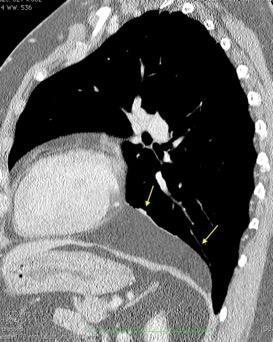

T. mixto de células germinales del testículo izquierdo

Nódulos pulmonares múltiples. (flechas verdes). Masas paratraqueales. (flechas amarillas). Dudoso ensanchamiento retrocrural (flechas negras). sigue….

Ttawfik A et al. Trans-diaphragmatic Pathologies: Anatomical Background and Spread of Disease on cross-sectional Imaging. Current Problems in Diagnostic Radiology. 2021.

T. mixto de células germinales del testículo

izquierdo Metástasis pulmonares. (flechas verdes). Ganglios paratraqueales. (flechas amarillas). Ganglios retroperitoneales (flechas negras)

Tawfik A et al. Trans-diaphragmatic Pathologies: Anatomical Background and Spread of Disease on cross-sectional Imaging. Current Problems in Diagnostic Radiology. 2021.